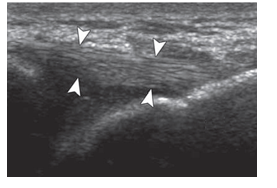

-Refer to the figure. What is the structure between the arrowheads?

A) Muscle

B) Ligament

C) Bursa

D) Subcutaneous fat